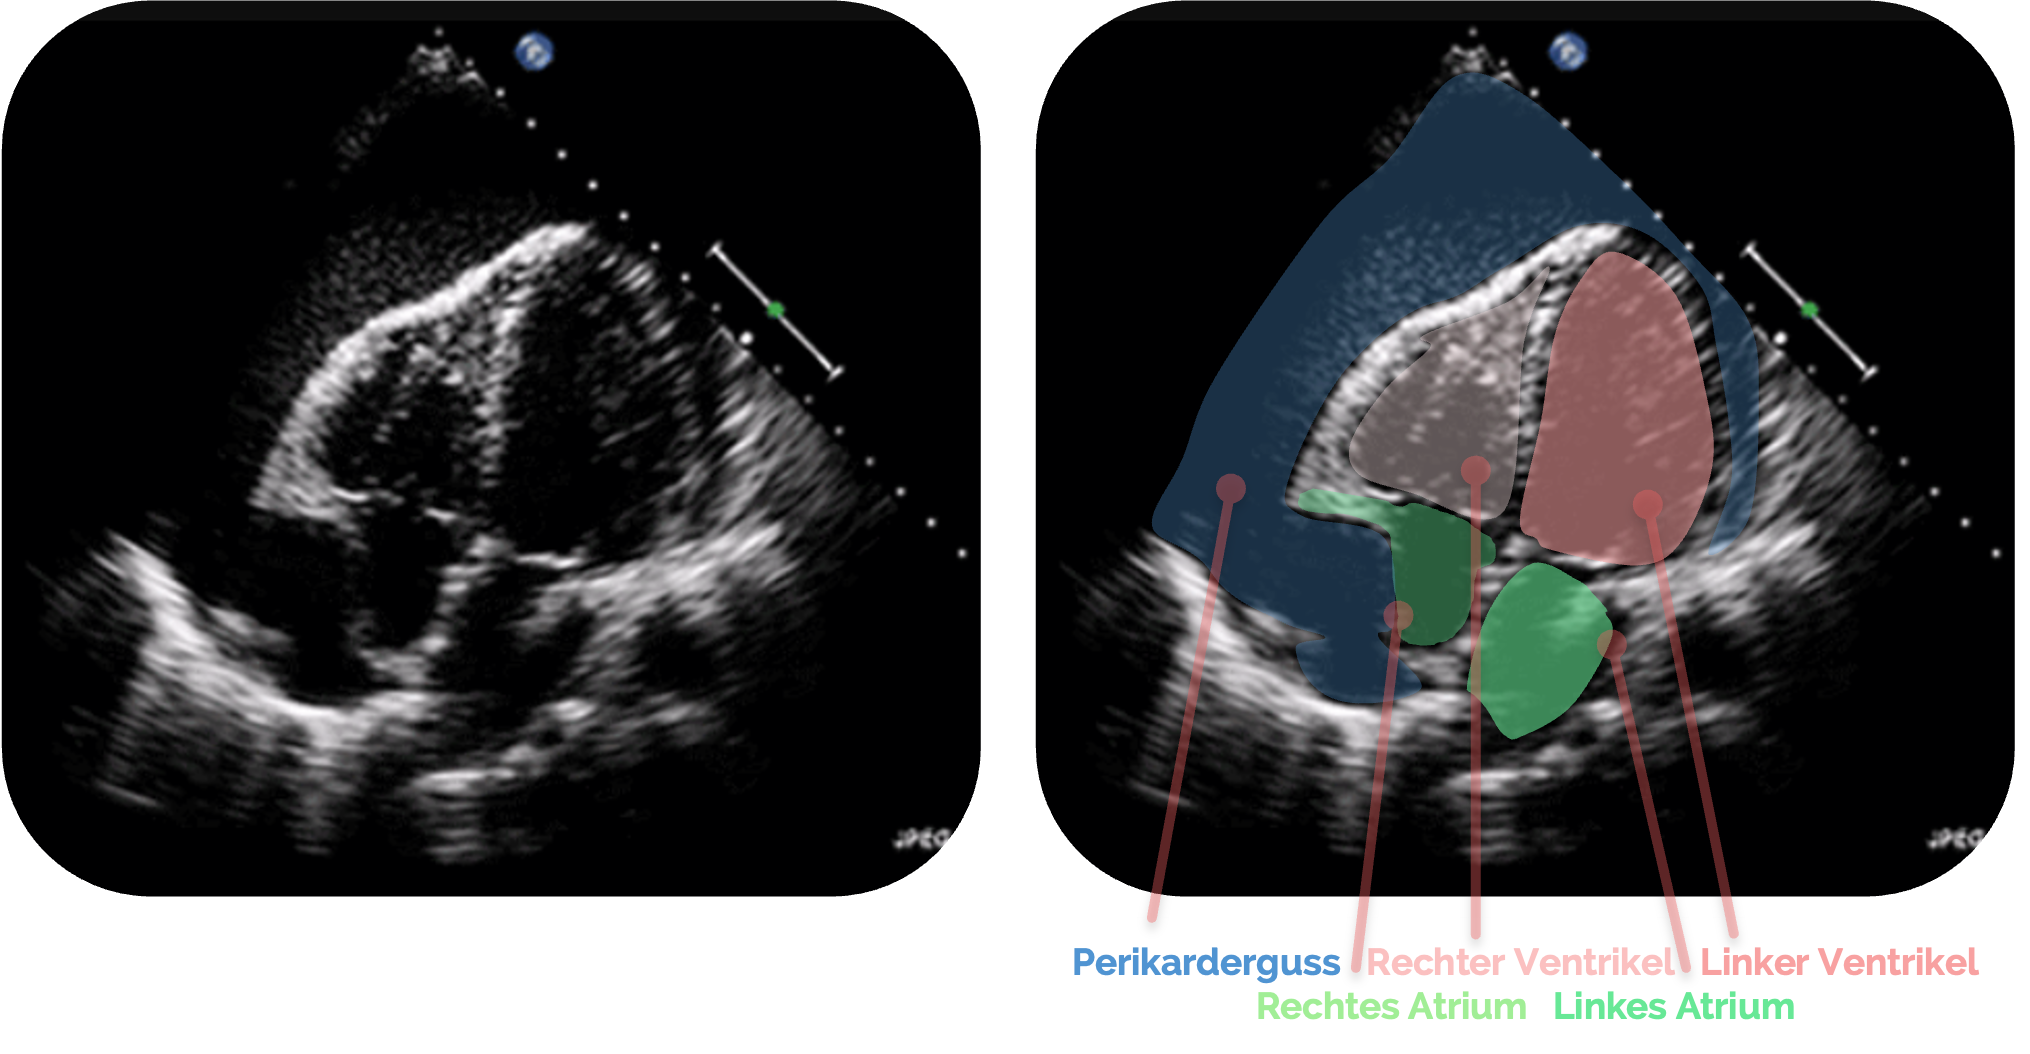

Perikarderguss

Sonographisch zeigt sich ein Perikarderguss als echoarmer (dunkler) Spalt zwischen dem Myokard und der echoreichen (hellen) Begrenzung des Perikards

In der subxiphoidalen Projektion liegt der Erguss zunächst meist posterior des Herzens und breitet sich mit zunehmender Flüssigkeitsmenge zirkulär

Das Perikard

Eine geringe Menge Flüssigkeit (10-50 ml) ist physiologisch und manchmal als sehr feiner Spalt darstellbar.

Die Menge des Ergusses (Messung immer am Ende der Diastole

- < 10 mm: geringgradiger Erguss, < 100 ml

- 10-20 mm: mittelgradiger Erguss, ca. 100-500 ml

- > 20 mm: hochgradiger Erguss, >500 ml

Neben der Ergussmenge ist für die klinische Relevanz vor allem die Füllungsgeschwindigkeit und die Compliance des Perikards

Selbst „kleinere“ Mengen von ca. 150 ml können in der Akutphase bereits hämodynamisch wirksam sein, während langsam entstehende Ergüsse ohne klinische Symptomatik mehrere hundert Milliliter enthalten können.

Relevant ist also vor allem der Druck, dem die Ventrikel standhalten müssen.

Pericardial effusion E00675 (CardioNetworks ECHOpedia).webm, CardioNetworks, CC BY-SA 3.0, https://creativecommons.org/licenses/by-sa/3.0, via Wikimedia Commons . Es wurden die Markierungen und Beschriftungen ergänzt.

Perikardtamponade

Wie beim Perikarderguss zeigt sich sonographisch eine anechogene oder echoarme Flüssigkeitsansammlung im Perikardraum, die das Herz zirkulär umgibt.

Im Gegensatz zum einfachen Erguss finden sich bei der Perikardtamponade